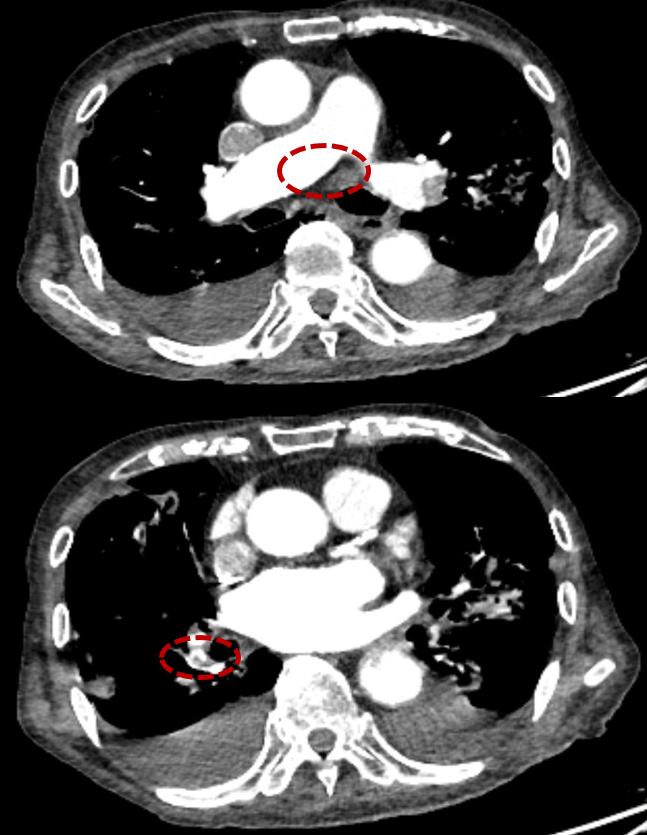

应用一段时间后,患者症状没有明显加重,但突然有一天,患者起床活动后突发晕厥,意识丧失数秒后自行恢复,这时我们再检测D-D,发现由1.25mg/L升至7.48mg/L;复查超声显示右侧小腿肌间静脉血栓形成;复查CTPA:左肺动脉较前新发血栓形成。

大家要重视到,这些血栓的形成对患者有很大影响,晕厥的发生可能就和血栓形成密切相关,这时我们是否加量低分子量肝素呢?如果不加量,血栓会继续加重怎么办?

考虑患者活动性出血,溃疡性结肠炎,高龄,激素治疗中:积极调整溃疡性结肠炎用药,同时申请输血2U(当时血红蛋白已经降到7克左右),当血红蛋白上升到8克以上时,把低分子量肝素改为2000iu q12h;在这个过程中发现出血没有增加,监测Hb等指标,患者症状逐渐稳定。出院后在院外延长抗凝。